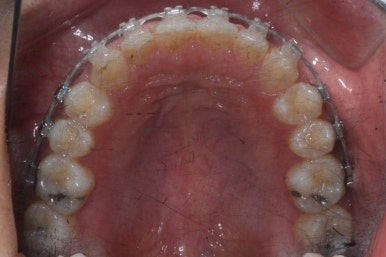

위 사진은 부산치아교정치과에 내원하셨을 대 당시의 입안 모습입니다.

치아들 사이에 전반적으로 틈이 많이 있는 상태입니다.